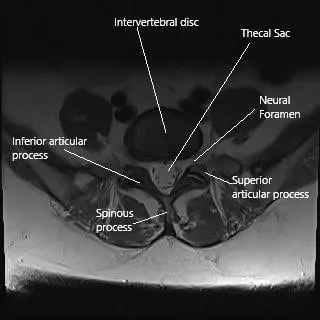

Axial section of the lumbar spine at L5 level.

Sciatica is most often caused by a prolapsed/slipped intervertebral disc. The prolapse of the soft tissue in between the vertebrae occurs commonly due to degenerative changes with age but may occur as a response to trauma/injury. The slipped disc may press upon the nerve roots and cause Sciatica. The symptoms usually get worse with bending forward, coughing, sneezing.

Spondylolisthesis occurs due to the displacement of the vertebrae over one another. The displacement may make the neural foramen and the central canal narrow causing Sciatica symptoms. The slippage may also cause prolapse of the intervertebral disc.